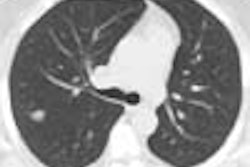

Baseline thoracic CT data are acquired over approximately 30 cm using a single-detector scanner (Picker 5000, Marconi Medical Systems, Cleveland, OH) using 120 kVp, 50 mA, 5-mm collimation and 3.5 mm reconstruction intervals.

Nodules detected at baseline are evaluated according to the criteria used by Henschke et al (The Lancet, July 10, 1999, Vol. 354:9173, pp. 99-105). If noncalcified nodules are found, the subjects undergo contrast-enhanced diagnostic CT using 200 mA, 5-mm collimation, and 2:1 pitch. The field of view was the same as that used in the screening exam to facilitate comparison.

So far, 1-6 noncalcified nodules have been detected in 30/92 subjects (33%) who have undergone CT. Among those 30 subjects, 3 had a single noncalcified nodule 1 cm or larger, two of which were malignant. These included a 12-mm peripheral squamous cell carcinoma, and a 28-mm nodule consistent at biopsy with small-cell lung cancer. The remaining 27 subjects had nodules smaller than 5 mm, and follow-up in 16 has showed no change in size, the authors wrote.